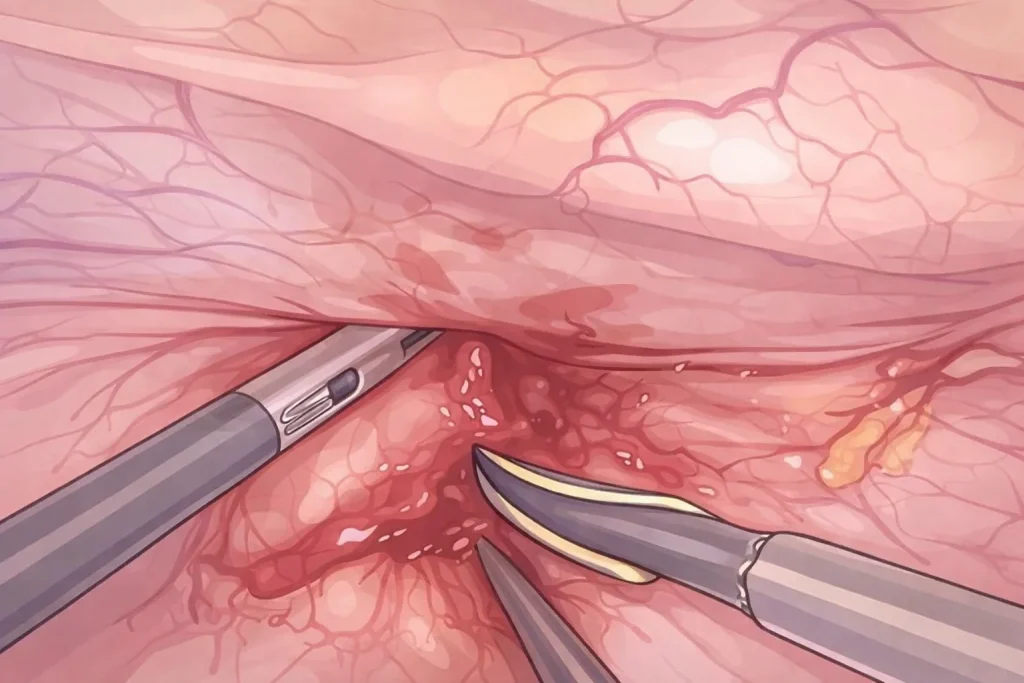

Παρακάτω παραθέτουμε εικόνες από λαπαροσκοπικό χειρουργείο μας. Τα χειρουργικά στάδια είναι η εκτομή του συριγγίου, η συρραφή του κόλπου και της ουροδόχου κύστης και η τοποθέτηση εντερικού λίπους (επίπλουν) μεταξύ κόλπου και κύστης για την καλύτερη επούλωση και μείωση των υποτροπών.